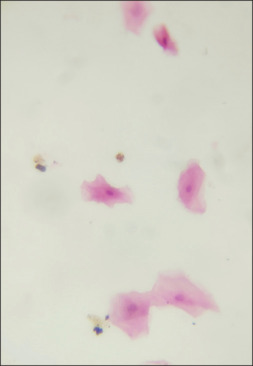

Background: This study aims to compare the efficacy between conventional exfoliative cytology (EC) and centrifuged liquid-based cytology (CLBC) in control, leukoplakia, and oral squamous cell carcinoma (OSCC) patients. Oral leukoplakia and oral cancer require an early definitive diagnosis for better prognostic outcome. Oral EC, a minimally invasive technique that involves the examination of desquamated cells from the tissue surfaces used as a method of early diagnosis. CLBC is a modified technique that is used to achieve improved quality of the cytology findings.

Materials and methods: A comparative study was done in 30 subjects, of which, 10 cases from control group, 10 oral leukoplakia, and 10 OSCC cases. These subjects were selected according to the appropriate inclusion and exclusion criteria. The cases in each group underwent conventional as well as CLBC. The comparison was carried out between these groups with respect to the cellular and background stromal factors. Appropriate qualitative evaluation of the samples was collected and statistical analysis was done using the Chi-squared test. The significance level of value was P < 0.05.

Results: Significant results were obtained for certain parameters such as cellular overlap clear background, uniform distribution in control, leukoplakia, and OSCC with a P = 0.004**, P = 0.001**, P = 0.006** using CLBC.

Conclusion: CLBC is better and give clearer vision as compared to conventional cytology and can be used in the early diagnosis.